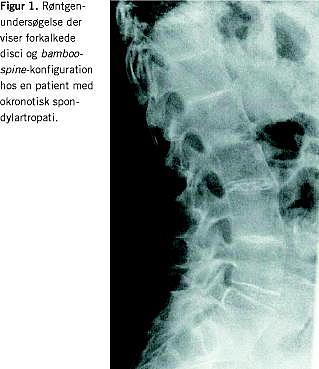

Symptomerne er smerter og stivhed i led og ryg. Ved røntgenundersøgelse af de vægtbærende led ses degenerative forandringer med afsmalnede ledspalter og subkondral sklerosering (okronotisk artropati). Ved okronotisk spondylartropati (OSpA) er columna afficeret, særlig toracolumbalt. Der ses svære discusdegenerationer ofte med ossifikation af nuclei pulposus samt andre degenerative forandringer. Kombineret discusdegeneration og -resorption fører til ankylose. Sekundær knoglenydannelse med udvikling af intervertebrale knoglebroer kan give et bamboo-spine -lignende billede. Ved involvering af sacroiliacaleddene (SI-leddene) ses subkondral sklerosering, men aldrig aflukning af leddene. Symfysen kan også være sæde for forandringer. Forandringerne i det aksiale skelet kan til forveksling ligne dem, man ser ved andre spondylartropatier, herunder AS, spondylose og diffus idiopatisk skeletal hyperostose (DISH). Værdien af magnetisk resonansskanning er uafklaret. Sjældent optræder kalcifikation af aortaklapperne. Nyre-, galde- og prostatasten er beskrevet. Ekstraskeletale manifestationer i form af entesopati, uveit, hud- og slimhindeforandringer forekommer ikke. Påvisning af homogentisinsyre i serum og urin er diagnostisk for alkaptonuri. Biokemien er i øvrigt normal. Behandlingen er symptomatisk [1-5].

En 53-årig kvinde blev på mistanke om AS henvist til reumatologisk ambulatorium. Problemet var tiltagende smerter og stivhed i ryggen samt radiologiske forandringer i SI-leddene. Smerterne var uden inflammatorisk præg (ingen morgenstivhed og ingen bedring ved aktivitet). Hun rapporterede misfarvning af urin og sved. Patienten var i øvrigt rask. Tyve år tidligere var hun blevet kolecystektomeret på grund af recidiverende galdestensanfald. Klinisk fandt man svært nedsat bevægelighed i columna thoracolumbalis og tegn på artrose i knæleddene. Ørebrusken var gråsort pigmenteret, mens sclerae var upåfaldende. Der var normal hjertestetoskopi. Røntgenundersøgelse af columna og pelvis viste udbredt højdereduktion og udtalte forkalkninger af disci, sklerosering af tilstødende terminalplader af corpora og bamboo-spine -konfiguration lumbalt (Figur 1 ). Der var sklerosering og småerosive forandringer omkring åbentstående SI-led bilateralt, og i symfysen var der afsmalnet ledspalte, små subkondrale cyster og subkondral sklerosering. Hofteleddene var uden artrose. Røntgenundersøgelse af knæleddene viste udtalt artrose femorapatellart og -tibialt. En urinprøve blev ikke med sikkerhed misfarvet efter henstand. Almindelig blodprøvescreening viste normale forhold. Der kunne påvises homogentisinsyre i urinen. Patienten fik stillet diagnosen okronose og blev afsluttet med paracetamol og ibuprofen .